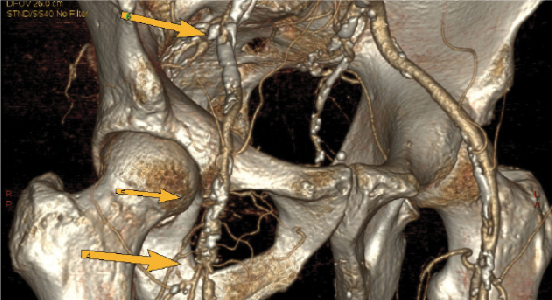

Computed tomography angiography with multidetector scanners has increasingly been in favor over traditional angiography with digital subtraction (see left photo). Met and coworkers performed a systemic review and meta-analysis evaluating the diagnostic accuracy of CTA for the detection of more than 50 percent arterial stenosis.18 They found the sensitivity and specificities for the aortoiliac, femoropopliteal and tibial arteries were 96 and 98, 97 and 94, 95 and 91 percent respectively. There was a slight overall decrease in both the sensitivity (92 versus 97 percent) and specificity (93 versus 98 percent) when evaluating images from 2-4 slice multidetector CTA imaging versus 16-64 slice multidetector CTA imaging respectively.

However, the reliability of CTA does suffer when discerning heavily calcified vessel walls from IV contrast, making interpretation sometimes challenging. Another limitation of CTA relates to the significant artifact caused by any metal prostheses, making the study limited in its usefulness. Another issue is direct evidence from epidemiologic studies that the organ doses corresponding to a common CTA study (two or three scans, resulting in a dose in the range of 30 to 90 mSv) result in an increased risk of cancer.21

Overall, multidetector CTA is an emerging non-invasive modality that enables one to assess vasculature including the coronary artery anatomy. In comparison to conventional angiography or duplex ultrasound, multidetector CTA is less expensive, less invasive and faster.18